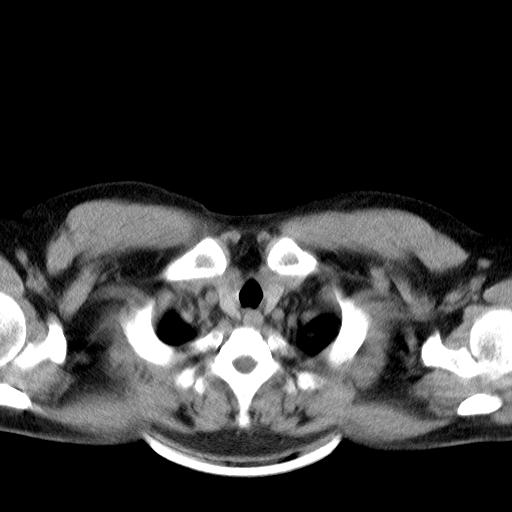

患者男性 35 主因发热咳嗽四天,血象不高,心肺听诊未见异常,无其它病史及传染病接触史。

两肺散在大小不等小结节影,下野较多,纵隔淋巴结增大。考虑:1、慢性血播性肺结核;2、霉菌病?3转移瘤待排。

两肺多发结节,部分病灶边缘不清,且示毛玻璃影。分布特点为沿血管支气管分布。

结合临床考虑;1,炎性肉芽肿性病变;霉菌?过敏性肺炎?2,韦格氏肉芽肿。3,转移瘤。